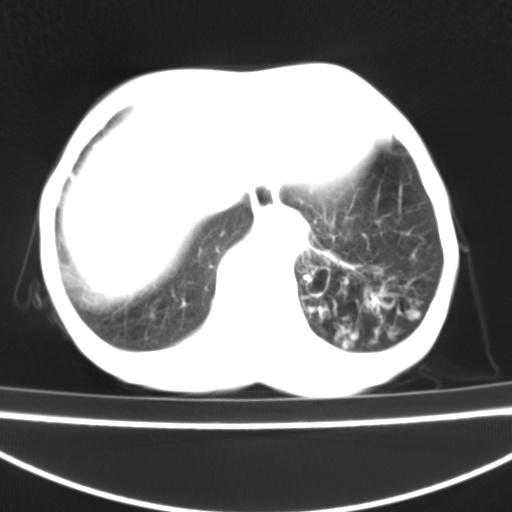

患者 女 67岁,反复咳嗽咳痰2年,加重伴喘及双下肢浮肿1月

诸大血管及f肺门血管增粗迂曲.左下肺多发薄壁空腔影.部分非也透亮度增高.薄曾扫描可区分肺气肿类型.考虑1.慢性支气管炎 2.左下肺支气管扩张 3.肺气肿 4 肺动脉高压5.是否有先心病病史

慢支炎、肺气肿、双肺感染、左下囊状支扩。

慢支、肺气肿、肺动脉高压;左下肺囊状支扩并粘液栓形成。